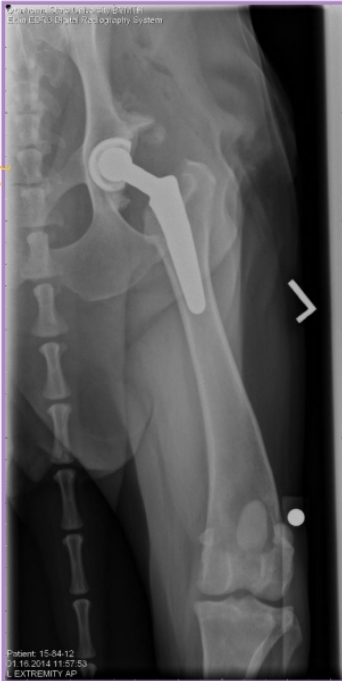

Total Hip Arthroplasty

Use: Salvage, replace end-stage joint with prosthesis

Pro: Near-normal fxn, Quick

Cons: expensive